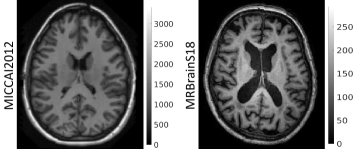

Refer to caption

Figure 1: T1-weighted MR images from two different, publicly available, datasets: MICCAI2012 and MRBrainS18 (on which we evaluate our method). It is evident that learning from one of these populations, and subsequently testing on the other is very challenging. The intensities are different by an order of magnitude, the bias is stronger in the MRBrainS18 subject. Additionally, age related change and pathology can be clearly seen, such as differences in ventricle size and white matter hyper-intensities, which further complicates the learning problem.

Challenges on medical image segmentation can be seen as lab experiments and – as with new medical therapies – there is a large gap to get from bench to bedside. CNNs excel in this context, factorising the commonalities in an image population of training data, which generalise to new data from the same population. They can struggle, however, when faced with new data that contain unseen features [10], e.g., a different contrast (Fig. 1). This scenario usually requires the model being trained anew, on that unseen image contrast. In fact, even without considering inter-individual variability (age, brain shape, pathology, etc), a CNN-based segmentation software has yet to be presented that is agnostic to the great variability in MR data [11]. Lack of such software is largely due to the limited amount of labelled data available in medical imaging, which is a clear obstacle to their generalisability. Some methods have been developed to address this problem, e.g., intensity normalisation [12], transfer learning [13] and batch normalisation [14]. Still, none of these methods are yet general enough to solve the task of segmenting across scanners and protocols. Recently, approaches based on realistic data augmentation have shown promising results [15, 16].